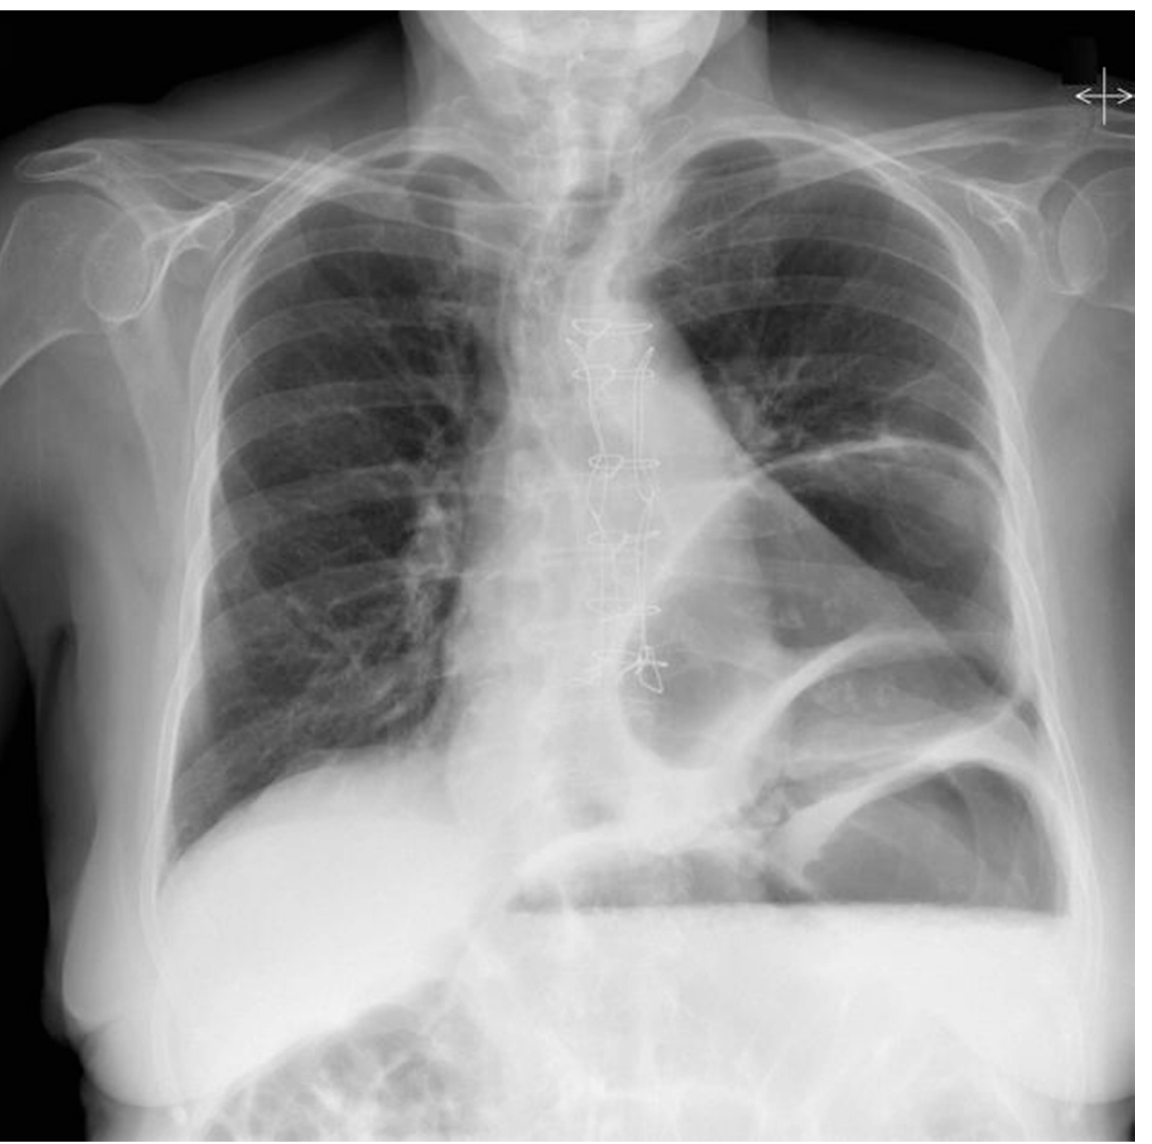

Q

diagnosis?

3 positive and two neg findings

gastric volvulus

Pos:

* hiatus hernia

* multiple bowel loops in intrathoraic region

* air fluid in lower loop suggesting obstruciton

* mediastinal shift

Neg

* no pneumothorax

* no free air under diaphragm